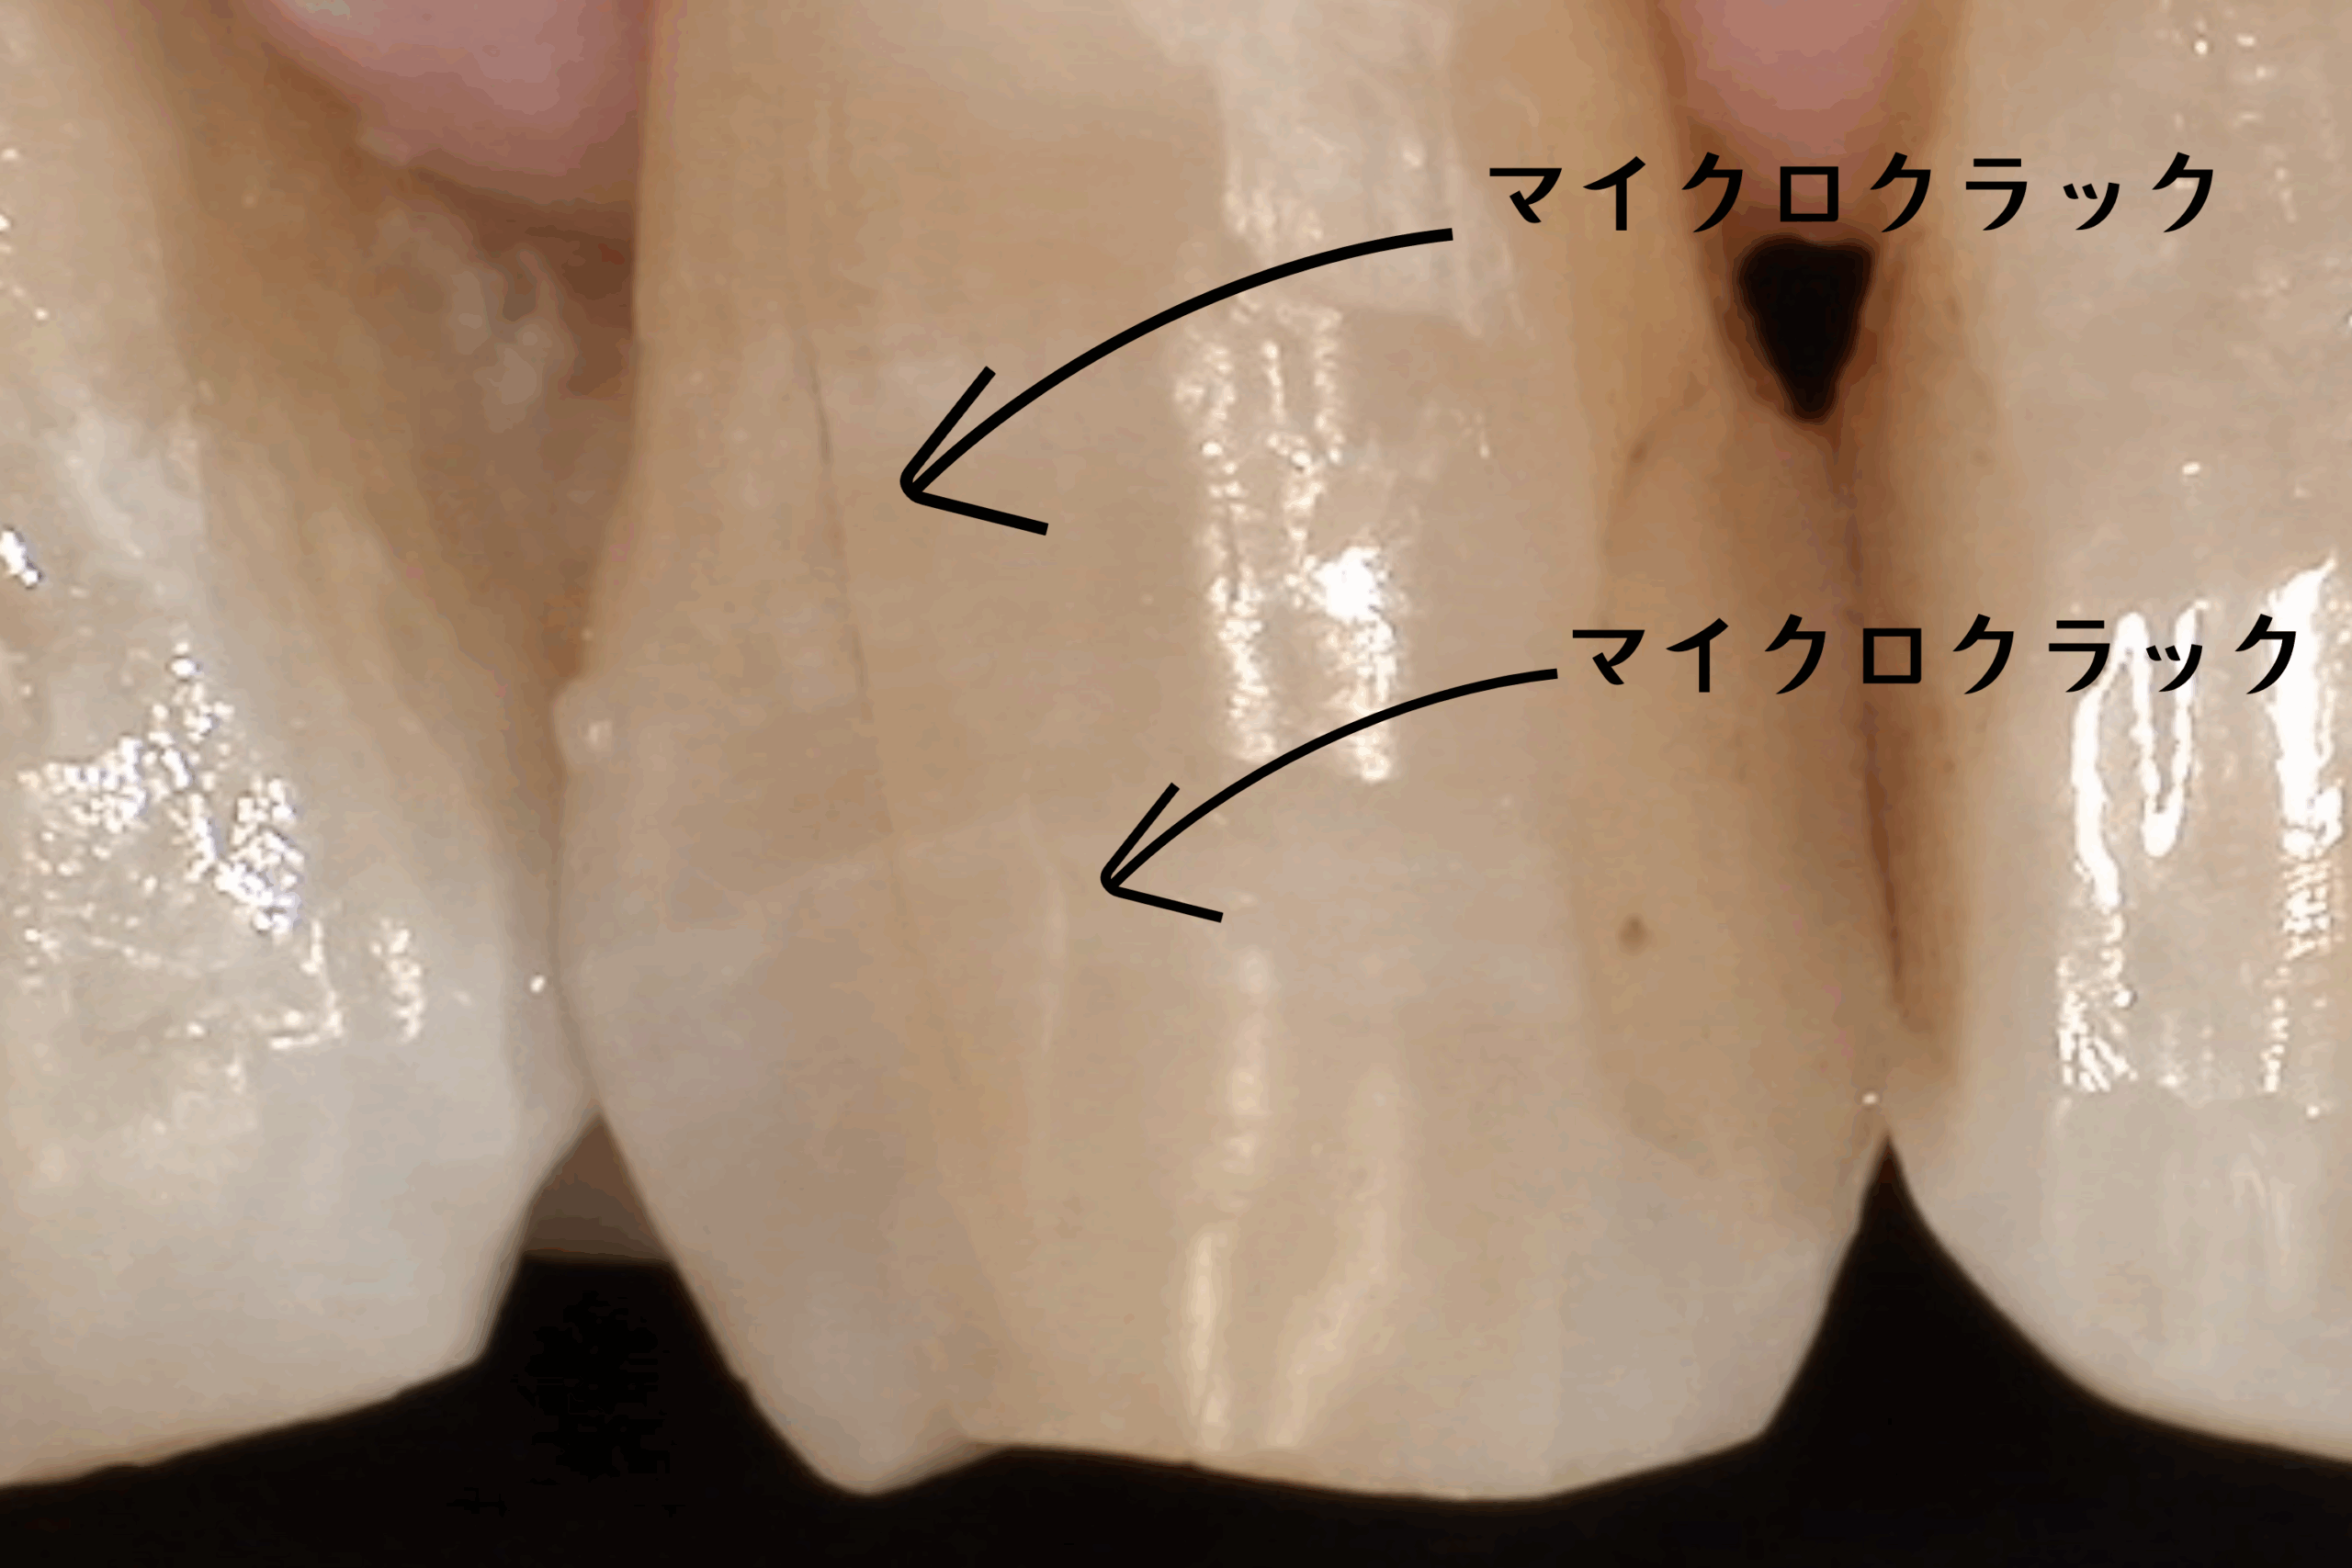

そう驚かれる方がほとんどです。それも無理はありません。なぜなら、このヒビは肉眼ではほとんど見えないレベルの細かさだからです。しかし、この小さな亀裂こそが、将来的に歯を失う原因になりかねないリスクであることを、皆さんに知っていただきたいのです。

1. 肉眼では見えない『マイクロクラック』の正体

毎日食事をし、噛み合わせることで、歯には想像以上の負担がかかり続けています。長い年月をかけて、硬いエナメル質には目に見えないほどの細かい亀裂が入っていきます。これを歯科用語で『マイクロクラック』と呼びます。

年齢とともに増える『歯の年輪』

正直に申し上げますと、マイクロクラックは誰にでもあります。 私たち人間も、年齢を重ねれば肌にシワができるように、歯にも経年変化としてのヒビが入ります。40代、50代と年齢を重ねるにつれ、マイクロクラックの数は確実に増えていきます。これはある種、歯が頑張って働いてきた証(年輪)のようなものであり、すべてのヒビが悪さをするわけではありません。

3. マイクロスコープがないと見えない世界

NK dental TOKYOでは、精密治療のために『マイクロスコープ(歯科用顕微鏡)』を常用しています。 なぜなら、『歯のヒビは、肉眼や一般的な拡大鏡(ルーペ)レベルでは見落とすことが多いから』です。

実際に、原因不明の痛みを訴える患者様の歯をマイクロスコープで拡大し、強い光を当てて観察すると、驚くような光景が見えてきます。 健康そうに見える白い歯の溝に、まるで稲妻のように走る鋭いライン。 染色液を使って染め出すと、そのラインがくっきりと浮かび上がります。

「うわっ、こんなにヒビが入っているんですか…」

モニターでご自身の歯の状態を見た患者様は、皆様絶句されます。 しかし、現状を『視る』ことこそが、治療の第一歩なのです。